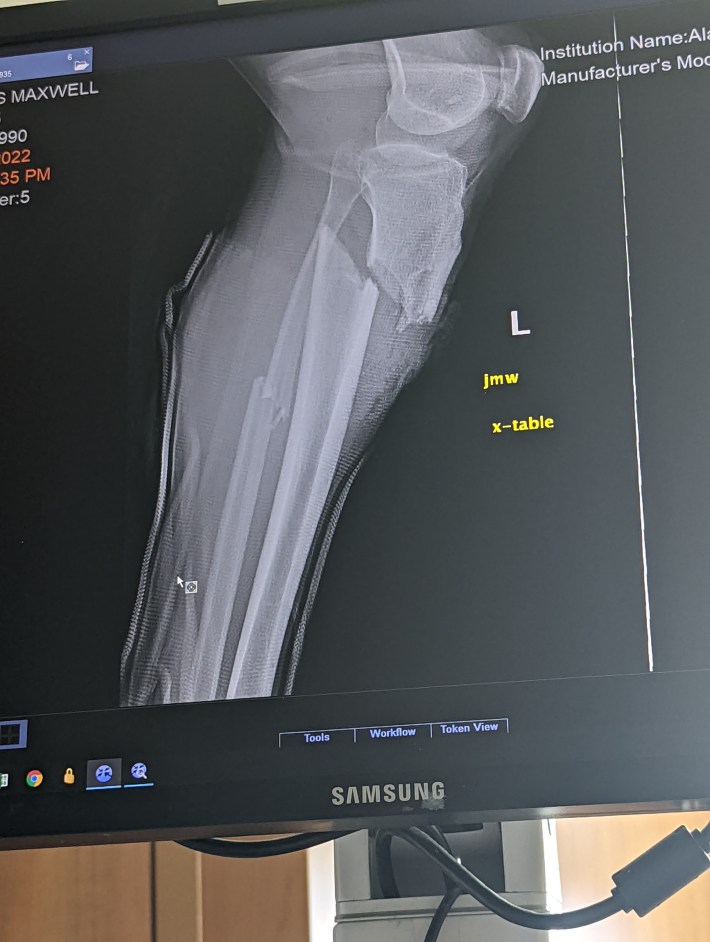

MD: The ambulance finally came. They cut my clothes off and loaded me onto a gurney. Getting loaded onto the ambulance was incredibly painful, getting moved with my leg broken. My back also hurt. Turns out my back was also broken, with a burst vertebrae. And the next day, I told the doctors it hurts when I move my arm. I had a broken collarbone too. They were most worried about my leg. They kept checking the pulse in my leg.

MD: Yeah, they were worried about that. That night, I went into surgery and got an external fixation. Two days later, they operated again and did an internal fixation.

SB: Plates and screws. Did the police come?